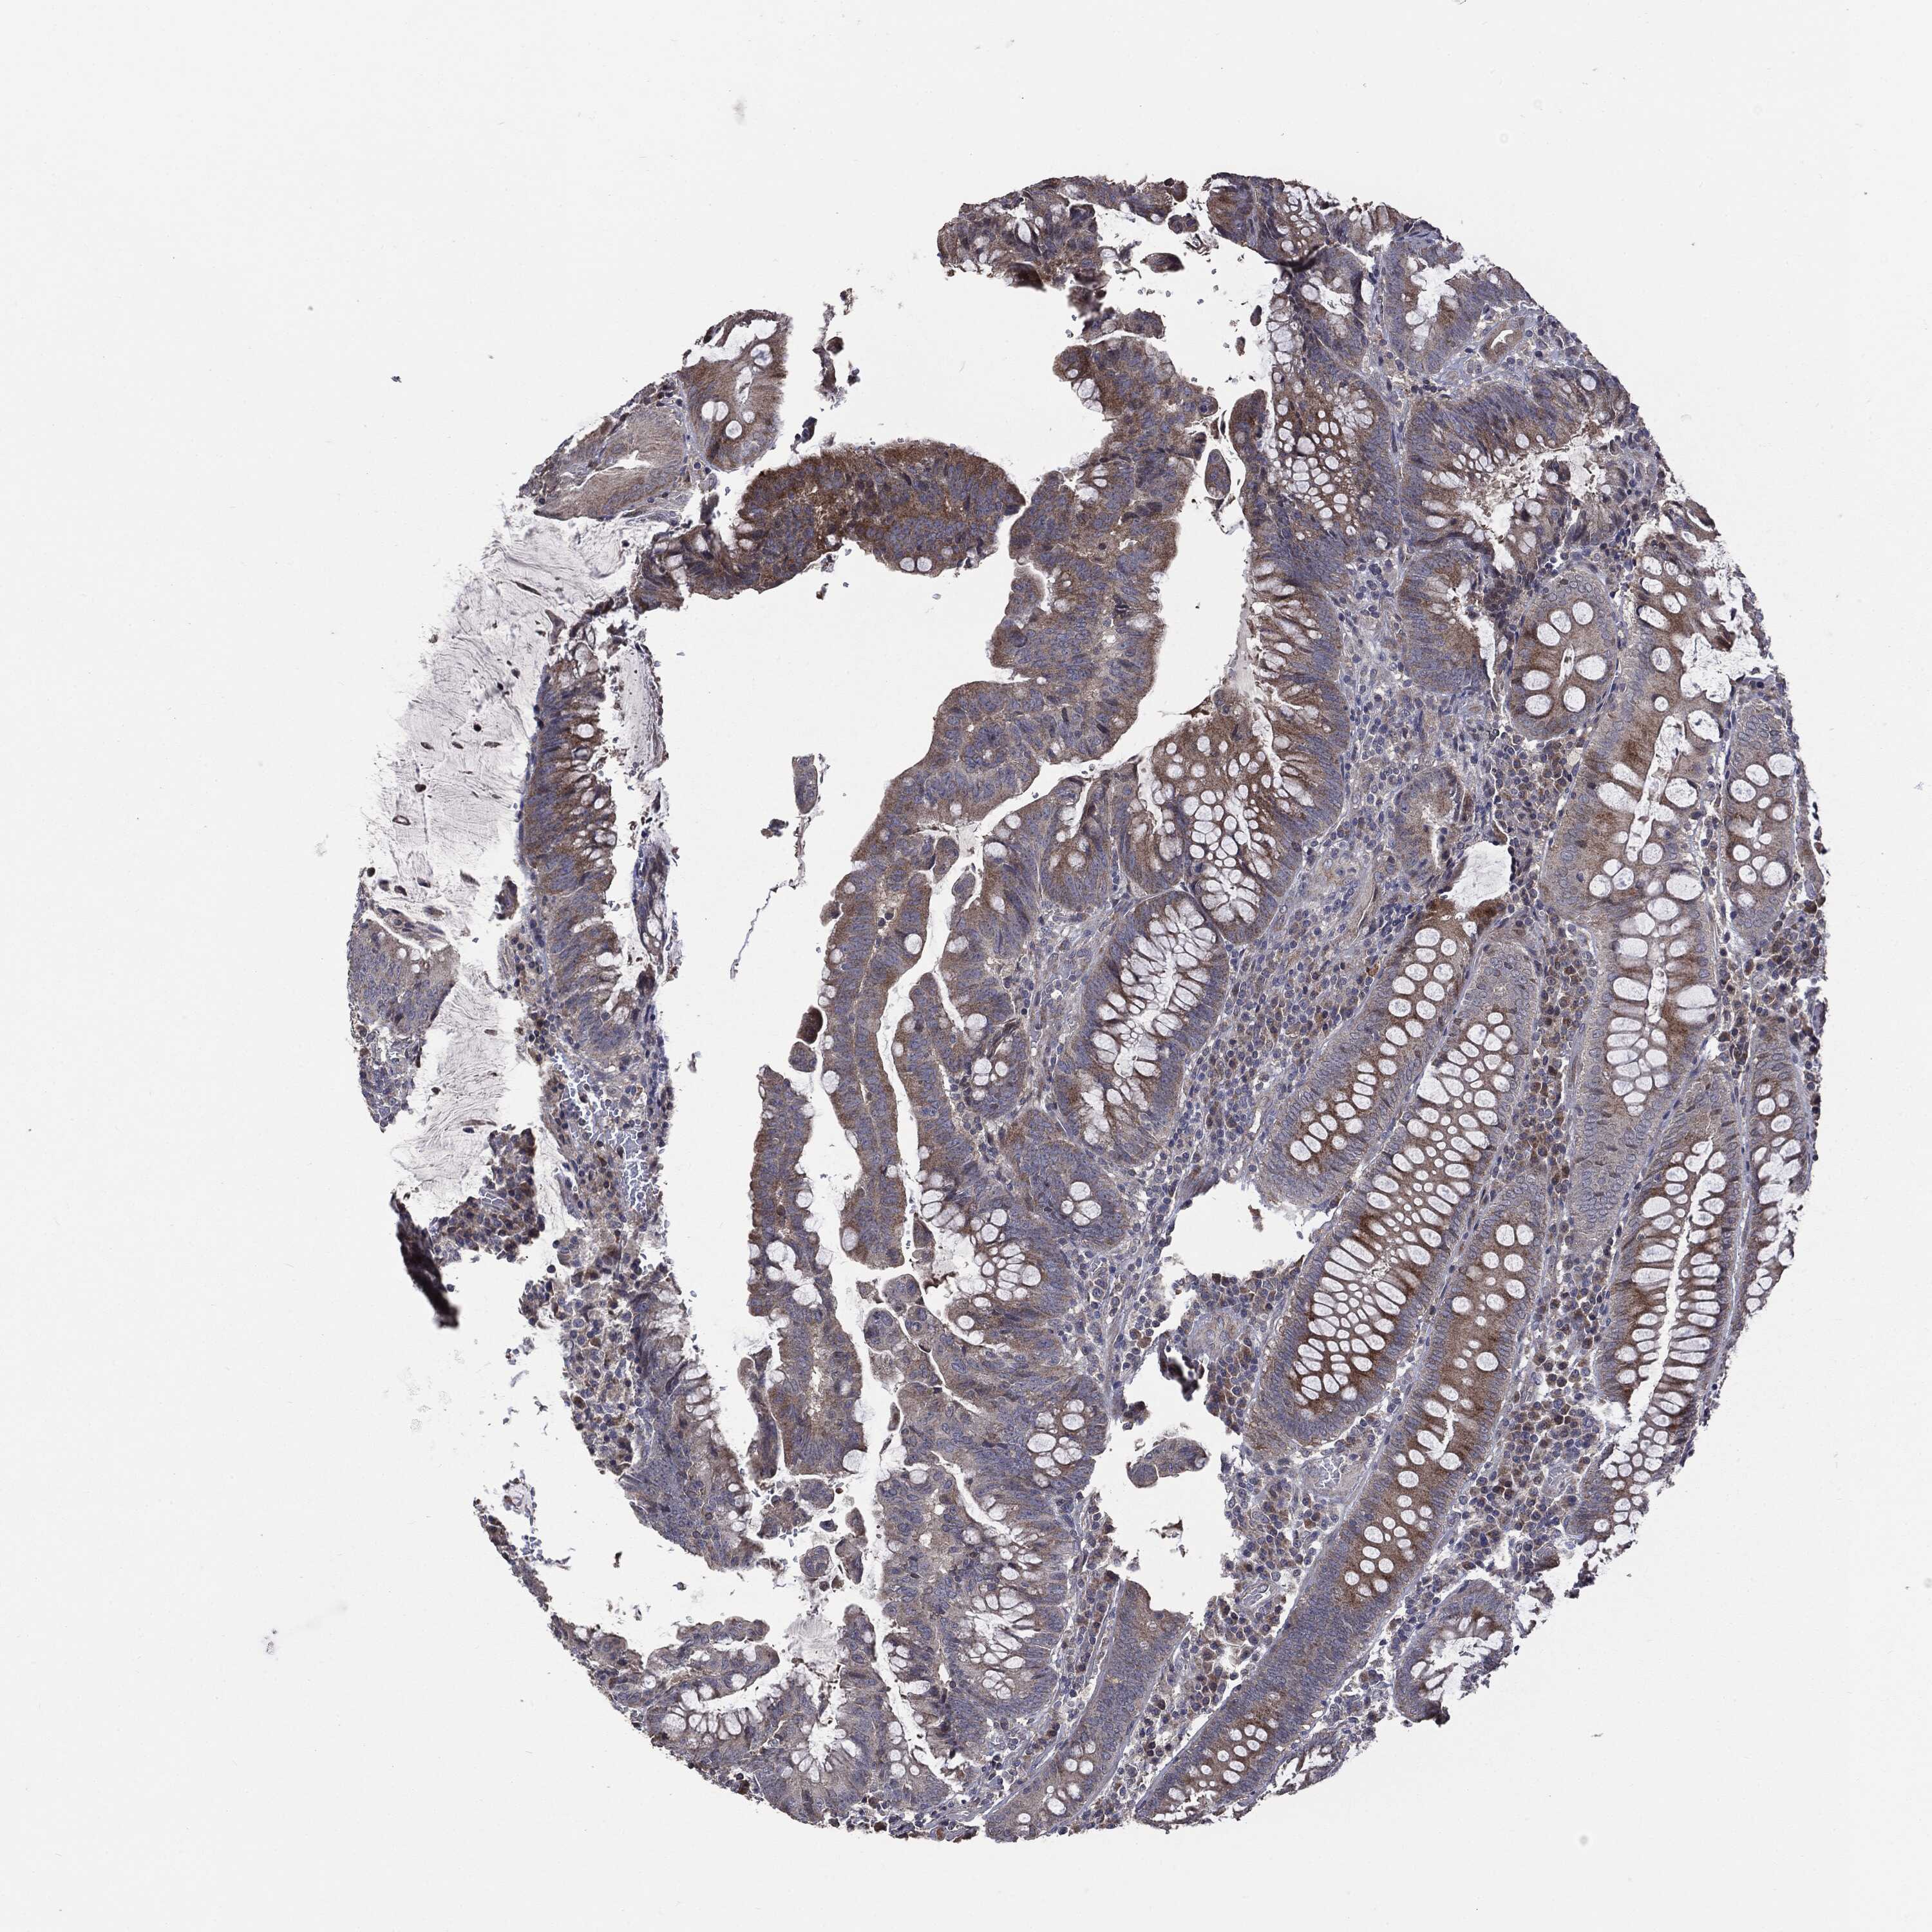

CANCER COLORECTAL CANCER Show tissue menu

Colorectal cancer

Human cancer

Colon adenocarcinoma